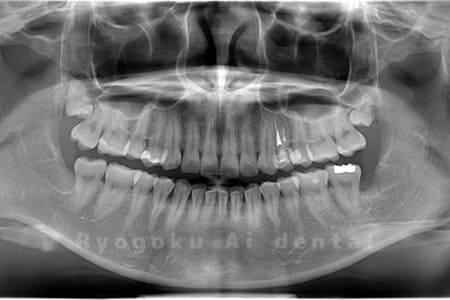

Case05

- 原因

- 下顎の親知らず2本

- 治療内容

- 下顎の親知らず2本を抜歯したケースです。

<リスク・副作用>

手術後は痛み、腫れ、痺れなどの副作用が生じる場合があります。